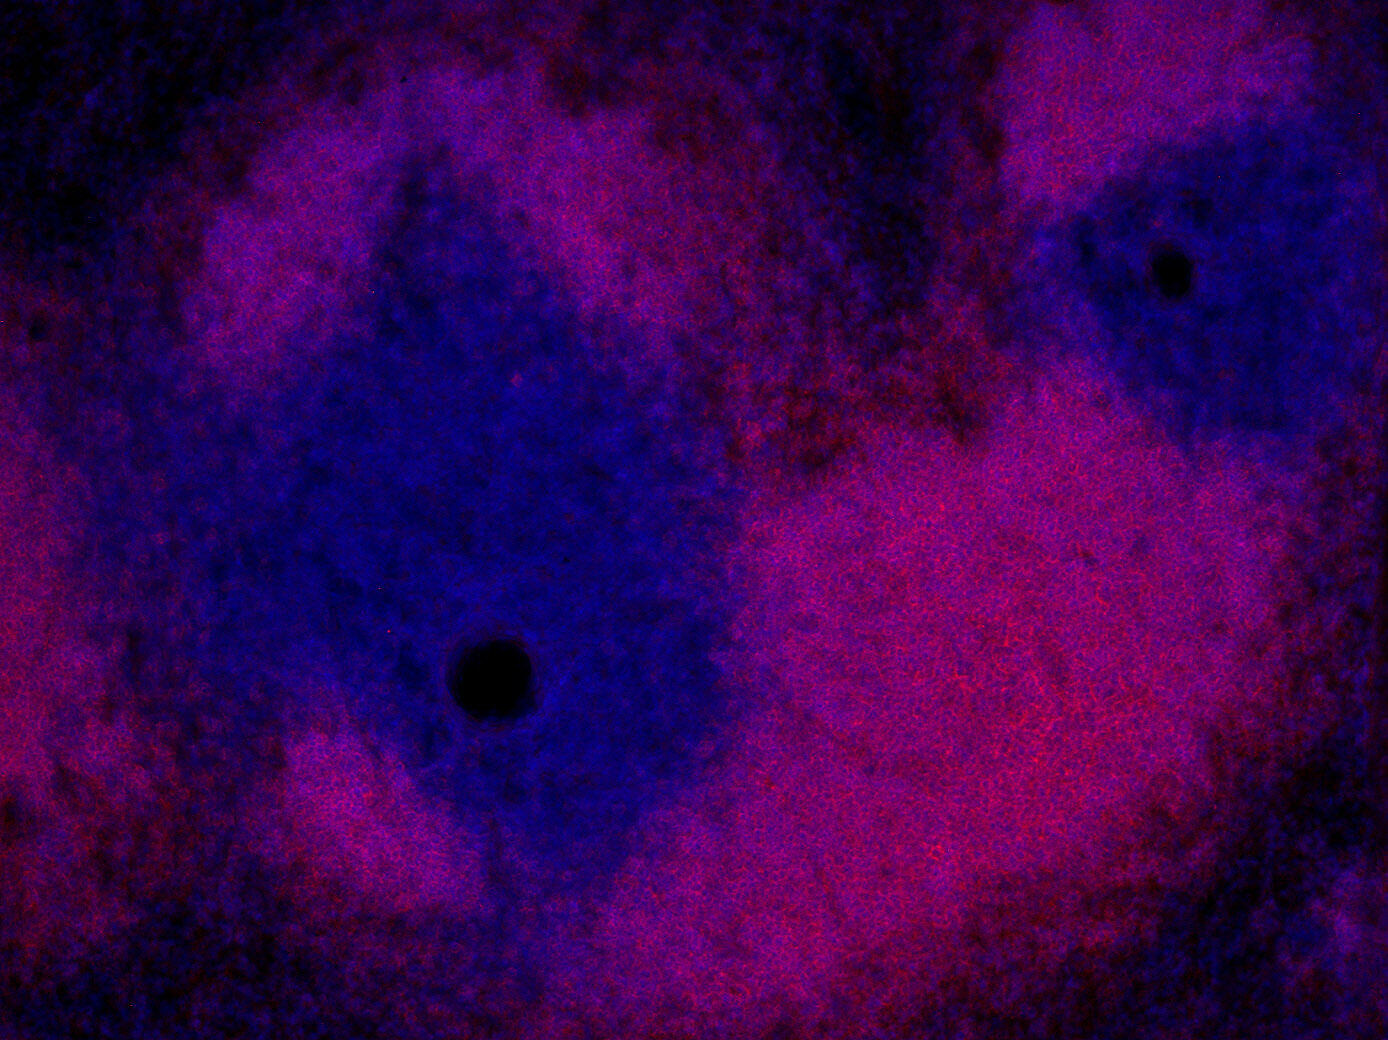

Indirect immunostaining of a formalin fixed paraffin-embedded mouse breast cancer model with rabbit anti-mouse CD19 (cat. no.: HS-439 003; DAB). Nuclei have been visualized by haematoxylin staining (blue).